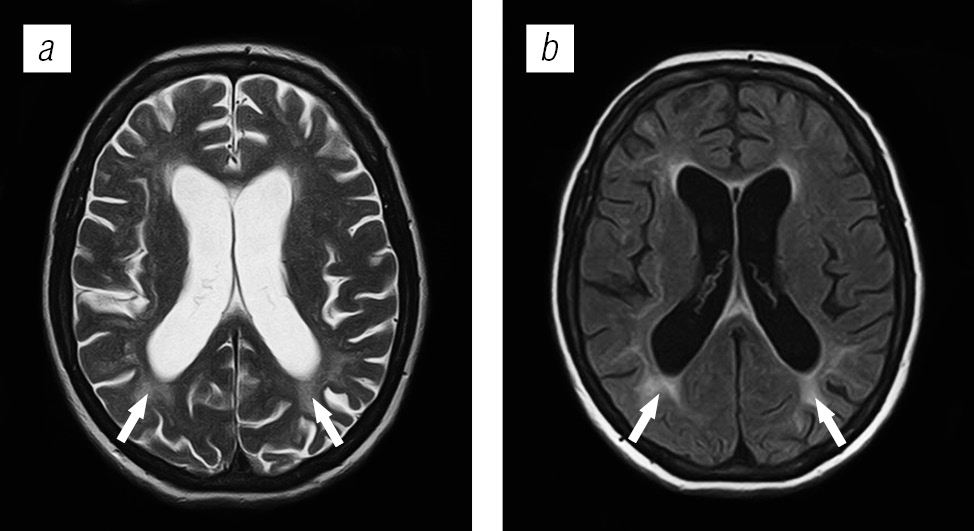

Структура поражения головного мозга у ВИЧ-инфицированных больных имела различную природу: в 54,4 % случаев обнаружены признаки оппортунистических и вторичных заболеваний, в 24,9 % — признаки ВИЧ-энцефалопатии, в 13,2 % — признаки неспецифических изменений мелких сосудов головного мозга, указывающие на преждевременное старение или аномалию развития; в 7,56 % признаки вовлечения головного мозга в патологический процесс не выявлены.